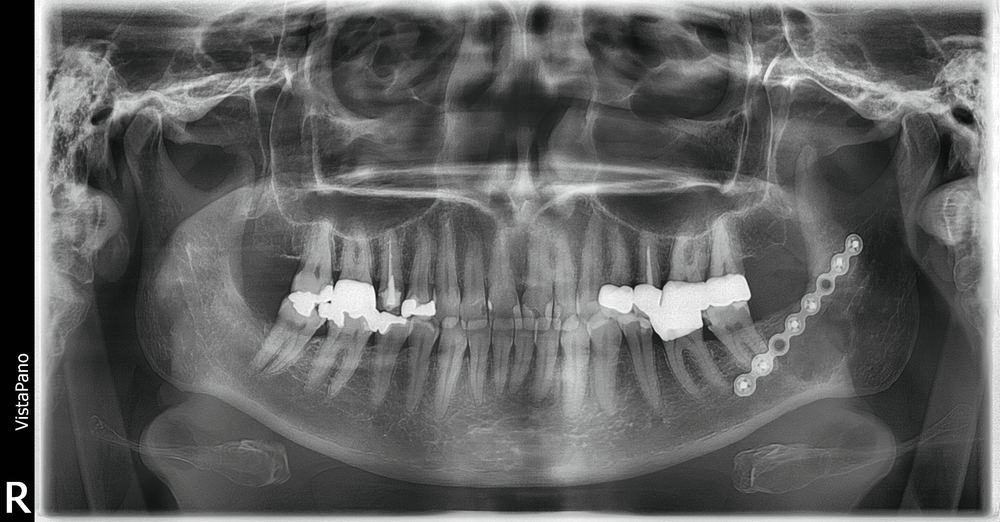

Eine 55-jährige, allgemeinanamnestisch gesunde Patientin stellte sich auf Überweisung ihres Hauszahnarztes mit einer unklaren Veränderung im Bereich des linken Kieferwinkels in der Klinik für Mund-, Kiefer- und Gesichtschirurgie des Universitätsklinikums Freiburg vor. Der Befund war bei einer Routinekontrolle in einer Panoramaschichtaufnahme (OPG) aufgefallen (Abbildung 1). Weitere Voraufnahmen existierten nicht. Radiologisch kam eine intraossäre, sklerotische Raumforderung mit zirkulärem, aufgehelltem Randsaum und überlagertem Nervus alveolaris inferior zur Darstellung. Klinisch bot sich ein unauffälliger Befund ohne knöcherne Auftreibung des Unterkiefers und mit blander Mukosa. Alle Zähne im linken Unterkiefer waren vital, die Sensibilitätstestung im Innervationsgebiet des linken Nervus alveolaris inferior zeigte sich regelrecht. Die Okklusion war habituell, die Mundöffnung ungestört.